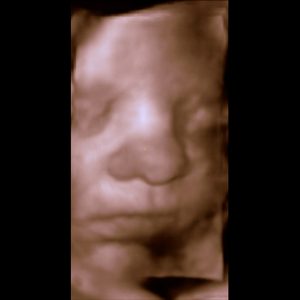

Η EMBRYOCHECK είναι εξειδικευμένη σύγχρονη μονάδα εμβρυομητρικής ιατρικής και εμβρυϊκής καρδιολογίας, αφιερωμένη στην υγεία της γυναίκας – μητέρας και του εμβρύου της και μελλοντικού παιδιού της. Ιδρύθηκε το 2006 και παρέχει υπηρεσίες που καλύπτουν όλο το φάσμα υπερηχογραφικής απεικόνισης στην μαιευτική και γυναικολογία. Βρίσκεται στο κέντρο της Αθήνας έναντι του Μεγάρου Μουσικής.